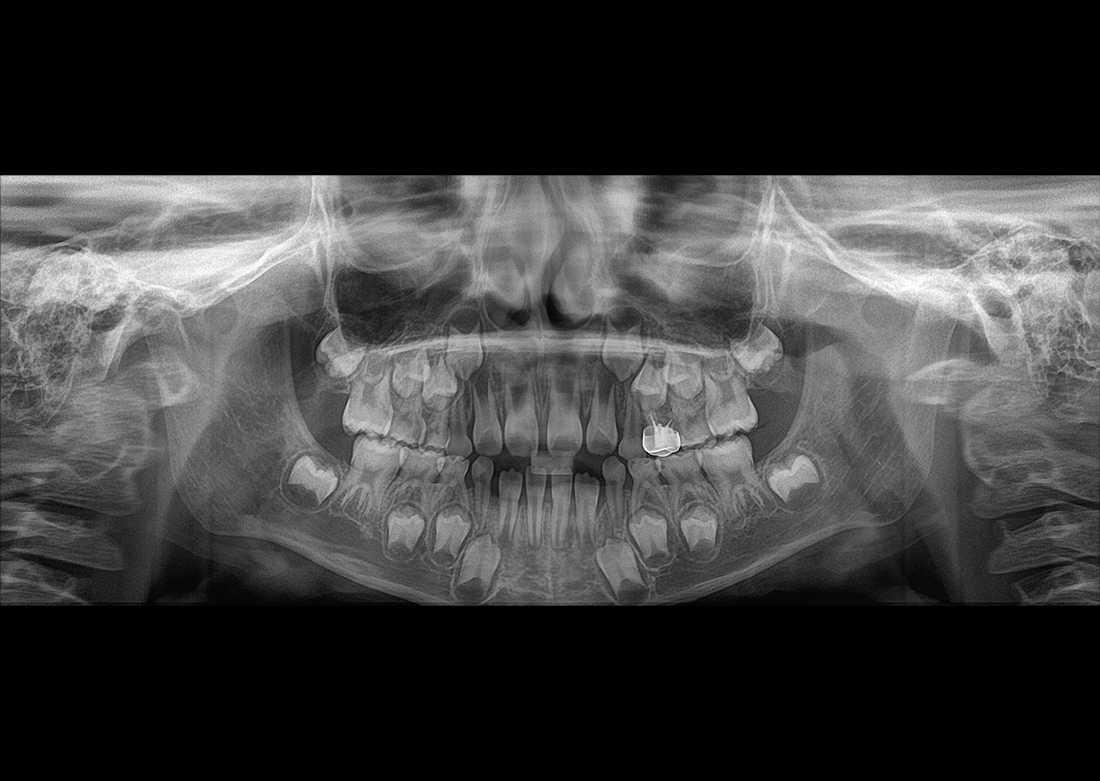

KLİNİK FOTOĞRAFLAR

Yılların tecrübesi ve geliştirdiği know-how teknolojileri ile muhteşem teşhis görüntüleri yaratmak Genoray firmasının herzaman gururu olmuştur..